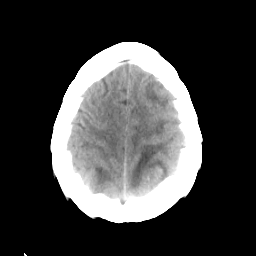

Sarcoma: Roentgen-ray CT -- Slice #20

[Home][Help][Clinical] Slice 20